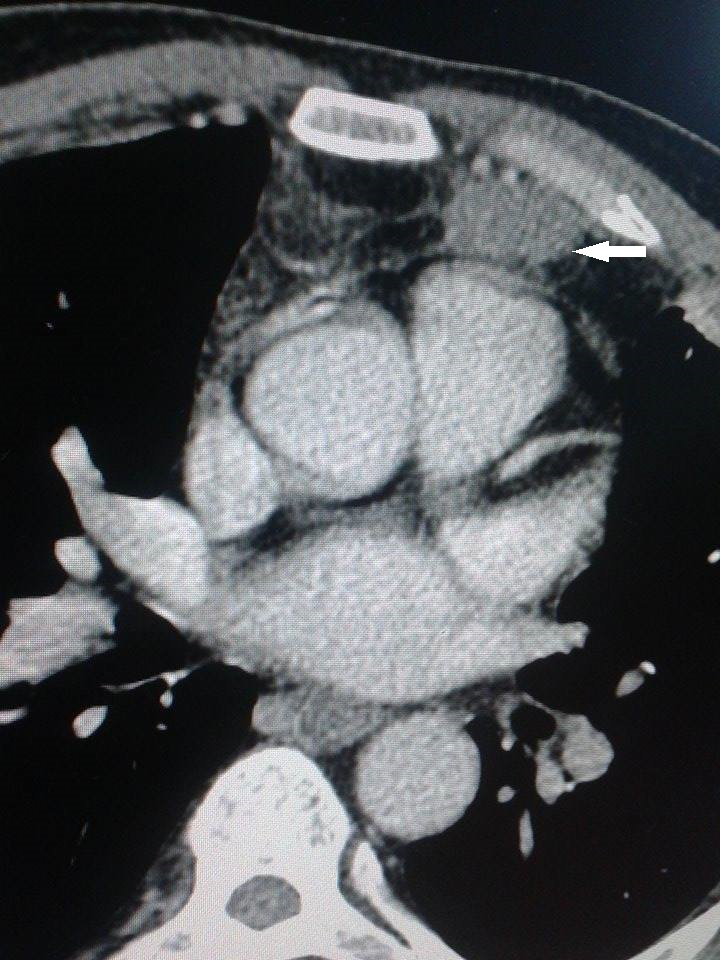

This is Mrs. BK, 62years old with hypercholesterolemia on treatment who consulted in our department for a back intervertebral left shoulder swelling which has been gradually increasing in volume for 7months. Clinical examination found her in good condition with a back painless mobile mass 12cm long, without signs of skin involvement (Figure 1). This mass had both soft and hard parts with a scar from a biopsy a month ago. Thoracic CT scan (Figure 2) showed a dorsal mass with fat and solid components of 86x73x30mm extending from the posterior arches of the 4th to the 7th ribs without their invasion with an extension to the latissimus dorsi. The staging investigations based on brain, abdominal and pelvic CT scan did not show secondary location. The pathological and immunohistochemical results of the biopsy was in favor of an invasive Pleomorphic Liposarcomas grade II extending its pseudo-capsule as classified by FNCLCC. The medical file was discussed in a multidisciplinary meeting for Thoracic Oncology Group and the indication of surgical resection was made. At surgery the patient was put in a right lateral position. A circumferential peri-tumoral incision respecting a margin of 2cm was performed. A one-piece resection carrying the tumor and part of the latissimus dorsi muscle was performed with a 2cm normal tissue margin. Deep cutting of para spinal and upper margins was also performed. Skin approximation with adjacent muscles mobilization reduced the surface of the wound by 2/3 (Figure 3). Pathological findings confirmed healthy resection margins and deep tissue cuttings that were free of any tumor. A skin graft was scheduled one month later.

Figure 2 Dorsal mass (white arrow) with fat and solid components of 86 x 73 x 30 mm with an extension to the latissimus dorsi.